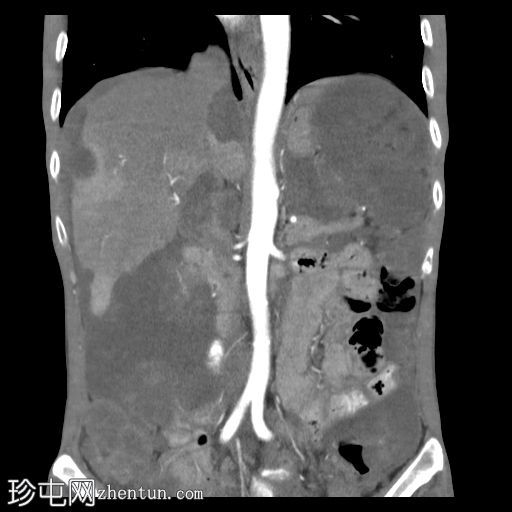

冠状位增强扫描(动脉期)

大网膜和肠系膜内可见低密度、不均匀的腹膜积液,脏器表面呈扇形凹陷,尤其以肝脏和脾脏最为明显。

可见双侧少量胸腔积液(右侧:1.0 cm;左侧:0.2 cm),右下后基底段被动性塌陷。

目前的CT影像特征符合PMP,提示黏液性物质继发性腹膜播散。